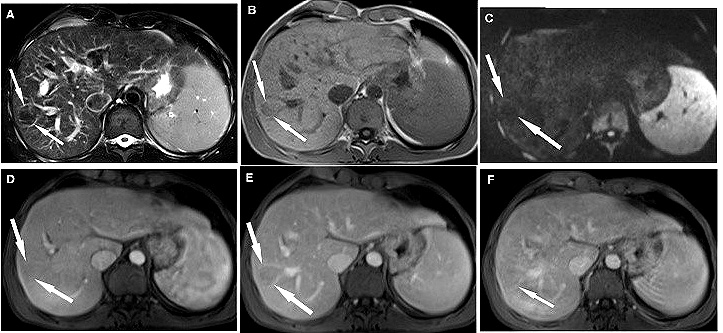

To show hepatic involvement in WD, Dohan (15) preformed a set of liver imaging manifestations and showed degree of intensity enhancement in nodules (Figure 4) (15). Authors considered focal liver lesion status and intensity variations in hepatocytes as important biomarkers for WD detection but found no correlation with confirmation of WD possibilities because other factors like alcohol consumption may also be the cause of presence of focal liver lesion.

Figure 4.A. Fat-suppressed MR image confirms hypointense liver nodule (arrows). B. The homogeneous and hypointense nodule (arrows) relative to the adjacent hepatic parenchyma. C. Nodule is markedly hypointense indicating free diffusion. D. Fat-suppressed image showing 3-D volumetric interpolated breath-hold examination and nodules (arrows) shows degree enhancement like adjacent hepatic parenchyma. E. Nodule (arrows) shows lower degree of enhancement compare to adjacent hepatic parenchyma. F. The nodule (arrow) is isointense to the adjacent hepatic parenchyma